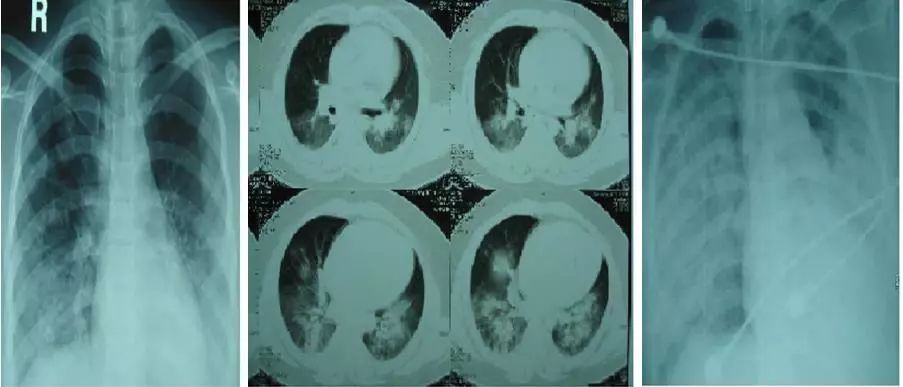

文献6:Henzler T, Meyer M, Kalenka A, et al. Image findings of patients with H1N1 virus pneumonia and acute respiratory failure[J]. Academic Radiology, 2010, 17(6):681-685.

乍一看,胸片是多发结节阴影。下面是CT:

沿着两侧肺门分布,乍一看,像肺水肿,但是心脏不大,下肺胸膜下病灶不少,发热、气促、磨玻璃,还是考虑病毒性肺炎。

下面这个患者就更不典型了:

什么情况?这不是朗汉斯组织细胞增生症?不是淋巴管平滑肌瘤?

NO 。

小叶间隔增厚,磨玻璃影,流感肺炎。

并且,居然有少量胸水!难得难得!

The patient underwent extracorporeal membrane oxygenation (ECMO) therapy 4 days after hospitalization.

入院后第4天,不得已用了ECMO治疗。

实变,多发,磨玻璃,晕征,呼吸困难,病毒性肺炎。

The patient was admitted to the intensive care unit and underwent extracorporeal membrane oxygenation (ECMO) therapy 2 days after hospitalization.

这个病人更严重,有糖尿病,入院后2天就不得已用ECMO治疗。